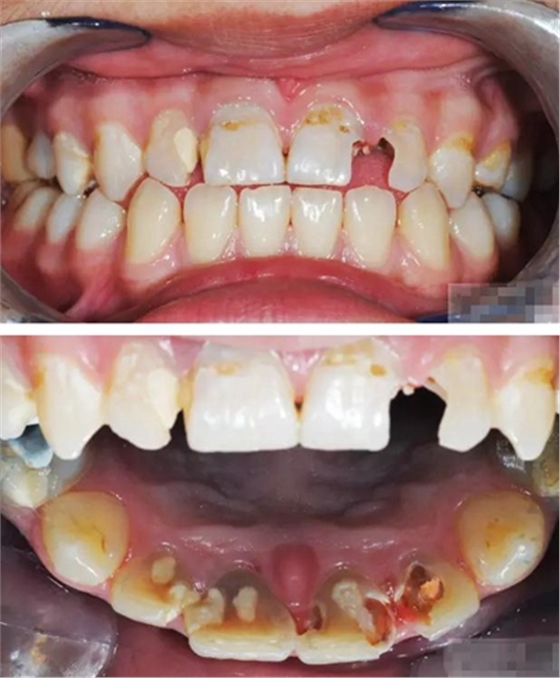

【主訴】上前牙充填物脫落兩個(gè)月

【病史】上前牙一年前行根管治療,充填物部分脫落,自覺(jué)影響美觀,從不敢笑,要求先行樹(shù)脂修復(fù)。(年齡:14歲)

【檢查】12,11,21,22,均行玻璃離子充填,各牙不同程度部分充填物脫落,探(—),叩(—),冷刺激無(wú)反應(yīng),無(wú)松動(dòng),牙齦顏色粉紅,質(zhì)地堅(jiān)實(shí)而有彈性,點(diǎn)彩正常,牙結(jié)石(—);牙髓活力測(cè)試無(wú)反應(yīng)。

【診斷】12,11,21,22牙體缺損